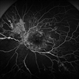

- Mike Mackens

- Imaging device

- Fundus camera

- Severe traction retinal detachment with diabetic retinopathy